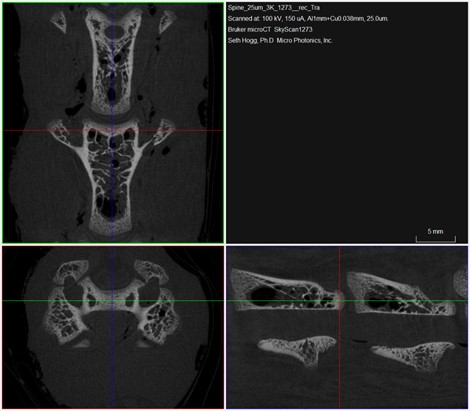

Figure 4: Planar views of individual vertebrae from the excised chicken neck sample

While the large overview scan is impressive, the SkyScan 1273 is still capable of high-resolution imaging, as shown with the results obtained on the vertebrae from the neck of the chicken (Figure 4).